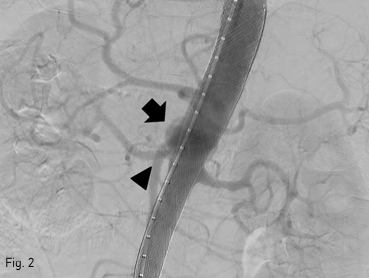

조영증강 CT에서 1.4 x 2.4 cm 크기의 낭성동맥류가 상부 복부 대동맥에서 보이고 상장간막동맥의 기시부 뒤쪽에 위치하고 있었다 (Fig. 1A-B). 그리고 우측 신장동맥 기시부에 국소 협착이 있었다.

Fig 1A

(A-B) Contrast enhanced CT and volume rendering image show a saccular aneurysm (arrows) involving the upper abdominal aorta, just posterior to the SMA origin.